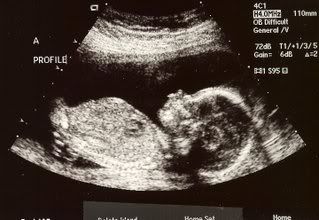

This is Baby A on December 21, also at about 330 grams.

They checked to make sure all our arms and legs and other parts were forming normally and were growing like they are supposed to-- we passed on all counts!